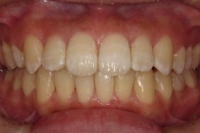

CASE2

↓前歯の歯並びを きれいに治したい。

(35歳/女性)

概要・担当医コメント:叢生・審美障害↑

動的治療期間13ヶ月(12回)/非抜歯/費用概算:55万円

上は固定式のブラケット矯正で,下は患者様ご自身が着脱するマウスピース矯正の治療を行いました.治療結果には大変満足されているそうです.